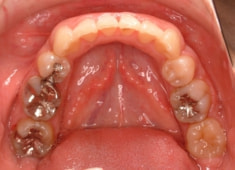

治療開始時